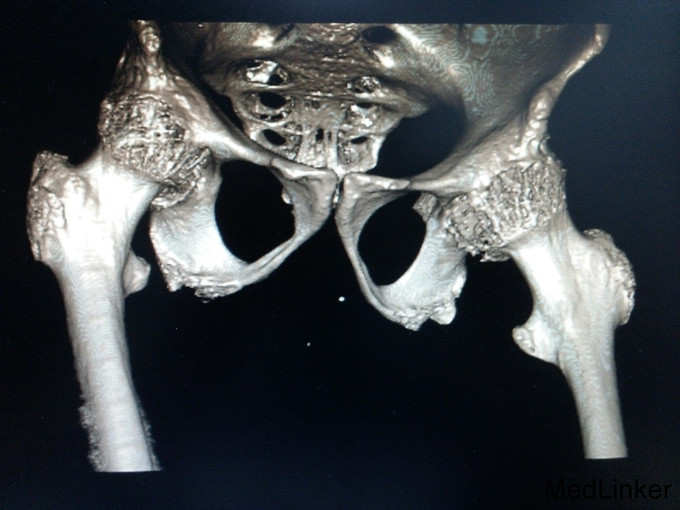

诊断:强直性脊柱炎(累及双侧髋关节) 患者腰骶部活动受限,影像学提示患者双侧骶髂关节间隙消失,且患者HLA—B27异常,强直性脊柱炎诊断明确。患者双髋关节间隙消失,活动度丧失,累及髋关节诊断明确。具有明确手术指症。患者既往关节鳞屑病,现控制稳定,经皮肤科会诊后排出手术禁忌症。由于经济稳定,患者及家属决定分次手术,本次手术暂行右侧人工全髋关节置换术。

讨论: 经验:强直性脊柱炎累及双髋的患者行全髋关节置换术时,显露及找到髋臼是手术的重点和难点。 1.显露。由于髋关节强直,失去活动度,助手在不能旋转大腿,造成显露困难。我们的做法是先充分显露小粗隆,沿小粗隆上方约2cm处截骨(一般常规于小粗隆上方0.5-1cm处截骨),充分离断头颈部,此时助手可通过内旋患肢,充分显露。下一步再按常规行小粗隆上截骨。 2.清除瘢痕组织。此类患者由于长期髋部强直,活动受限,周围往往会形成瘢痕挛缩,多以内收肌紧张常见。故显露的过程需彻底清除周围瘢痕组织。术中安装假体后测试关节各方西活动,若内收肌紧张,需行内收肌松解。 3.找髋臼。由于强直性脊柱炎累及髋关节需行关节置换的患者,往往头与髋臼已经发生融合,术中很难判断髋臼。若贸然凿除所谓的股骨头,很可能会破坏髋臼壁。故找髋臼时性循序渐进,逐渐凿骨找到髋臼。CT片显示头与髋臼底之间仍有间隙存在,故可推断圆韧带仍存在,这也是这类患者的特点。故逐渐凿除股骨头时,到达圆韧带的层面时就找到了髋臼底。此时可开始磨钻磨锉髋臼。从小号开始依次增大号数。 4.骨质。强直性脊柱炎的患者因长期服用激素类药物,骨量丢失较正常人较多,故髋臼骨质疏松明显,所以磨搓髋臼时需反转,防止骨量过度丢失,磨穿髋臼。 不足:1.术中由于患者左髋强直,摆放手术体位受限,不能维持身体中立位,身体后仰,术中安放臼杯时未能把握合适的前倾角度。 2.假体的选择。由于术前未认真评估股骨髓腔的形态,导致术中按常规选择股骨假体柄后,出现假体柄打入困难。该患者股骨髓腔形态呈烟囱型,最好选择直柄,打入后可更贴合,方便骨长入。